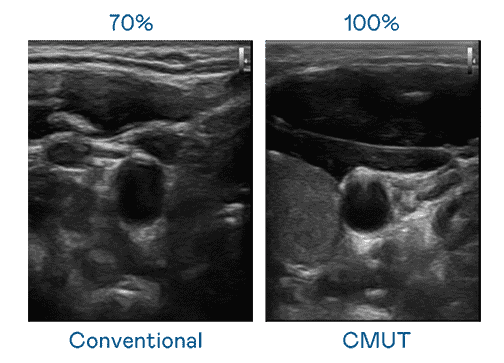

CMUT 技术是一种用电容式微机电元件来产生超音波讯号的技术。。。。与传统 PZT 压电式技术相比,,,,CMUT 频宽增加 30%,,,,更宽频的超音波讯号让影像解析度大幅提升,,是实现高影像品质医疗超音波扫描、、、、促进精准医疗发展的关键技术。。。

大频宽带来超清晰影像

超音波影像的解析度高低,,,,首先取决于探头能发出的讯号频宽。。。。开云电子 CMUT 可提供高清晰的超音波讯号,,提供高频宽、、、、高灵敏度、、、、影像纹理细节更高的超音波影像,,协助医护人员缩短影像判读时间及利用精准的医疗影像进行诊断。。